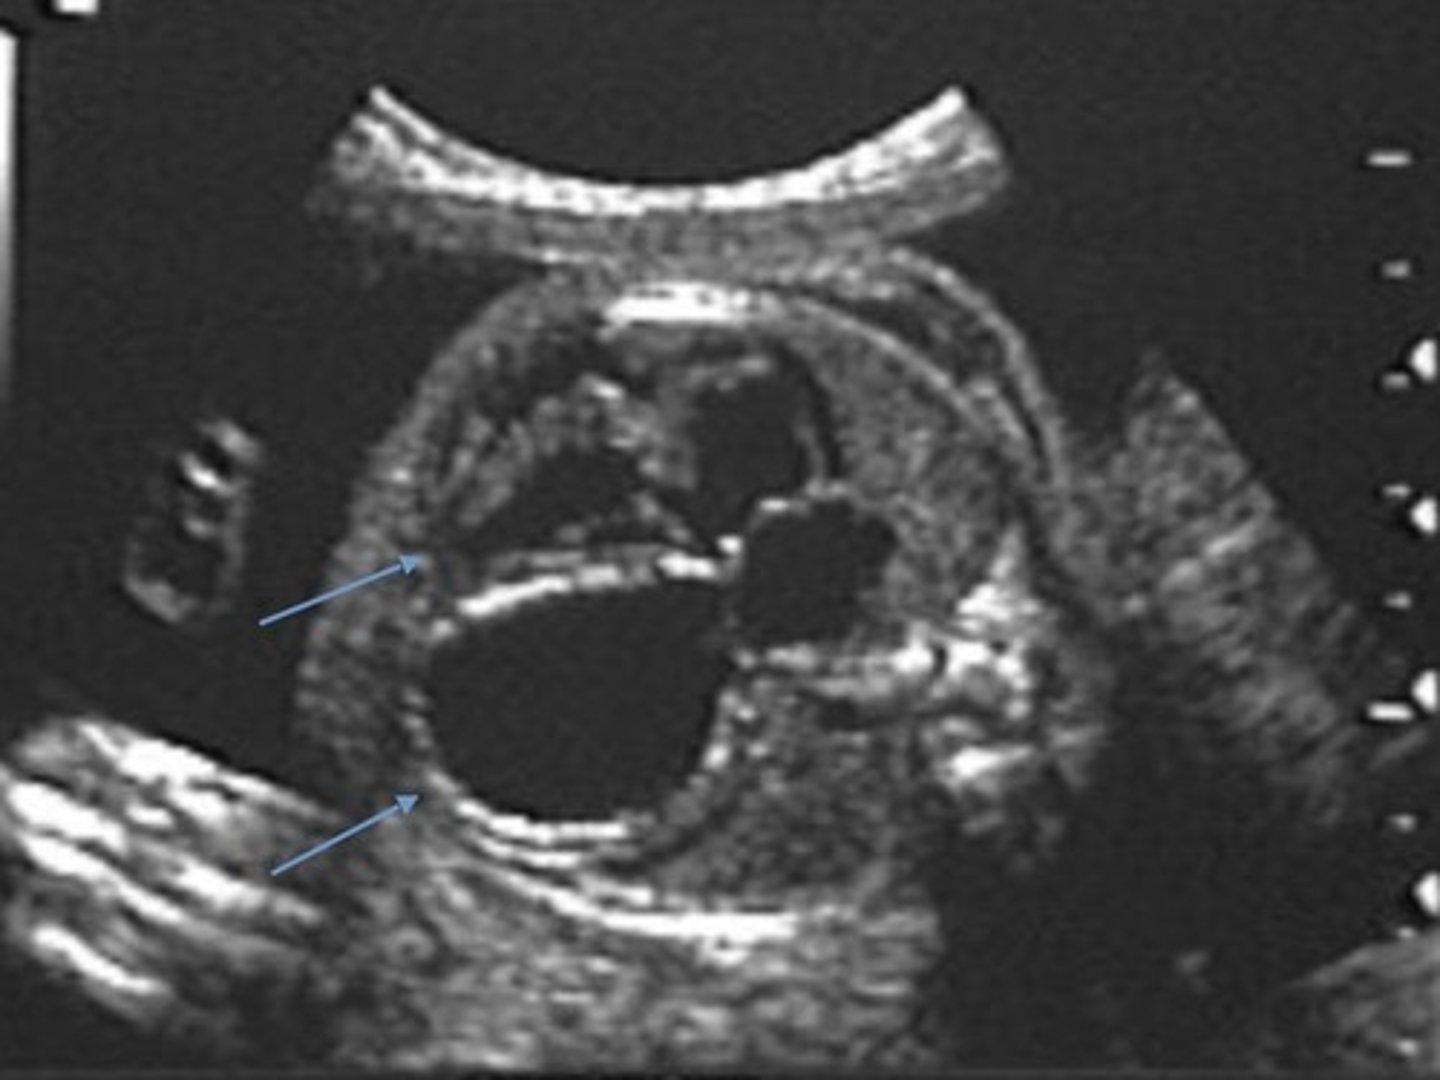

Ebstein's Anomaly

Best seen in 4 Chamber

Apical displacement of tricuspid valve -> TV is lower than it should be